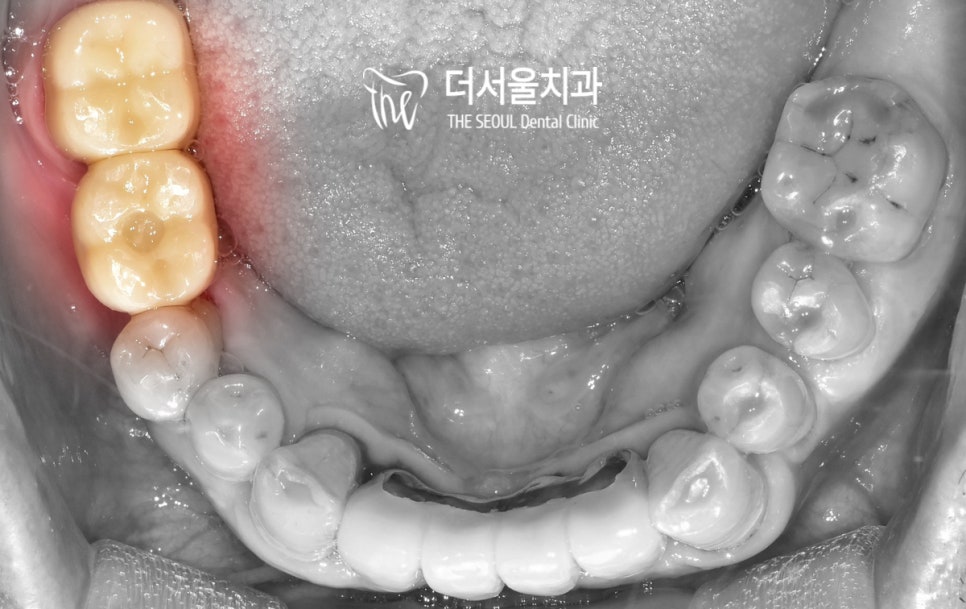

상악동거상술 및 임플란트 의 최종 과정입니다.

『완성된 크라운을 올려드려야겠죠?』

구강 내 모습이 확 바뀐 것을 확인할 수 있었습니다.

여러분들을 위해 비교 움짤을 만들어보았는데요.

이렇게 보니 변화가 더 크지 않나요?